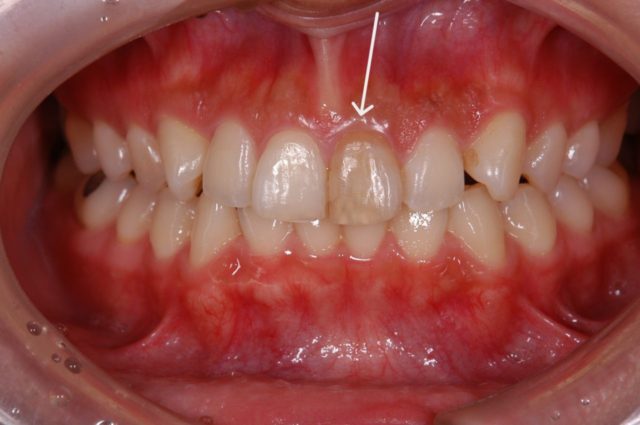

before

| 年代/性別 | 40歳 男性 |

| 主訴 | 右2番揺れる、左右1番やり替えたい |

| 治療方法 | 右2番インプラント及び、左右1番オールセラミッククラウンによる審美治療 |

| 治療期間 | 11ヵ月 |

| 費用 | 825,000円(税込) |